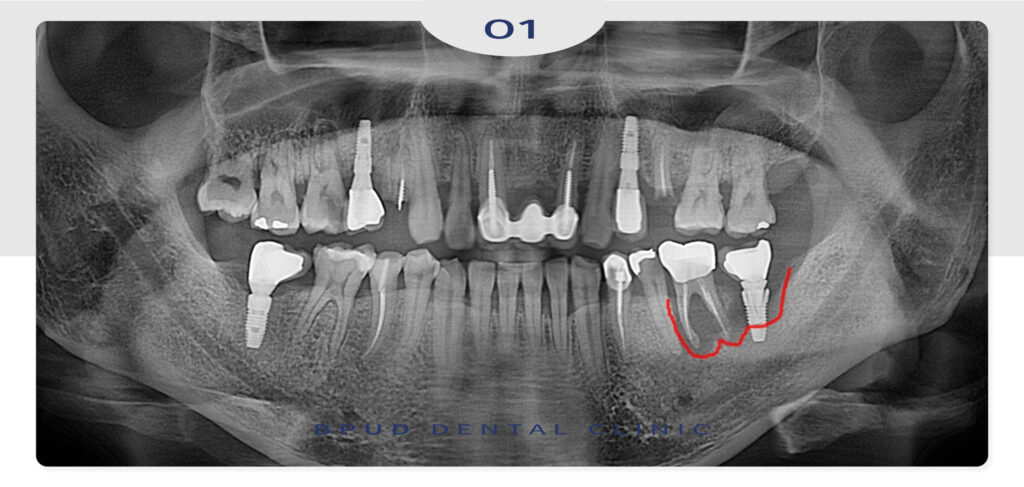

23.07.10

이어서 최종 보철물을 완성하고

오른쪽 위 치아들도 충치 및

치근단 병소로 인해 발치 후

상악동 거상술을 통해 임플란트

식립을 진행하였습니다.

마지막으로 오른쪽 아래 타원 임플란트

보철의 재제작과 앞쪽 어금니까지

크라운 재수복을 마쳤는데요.